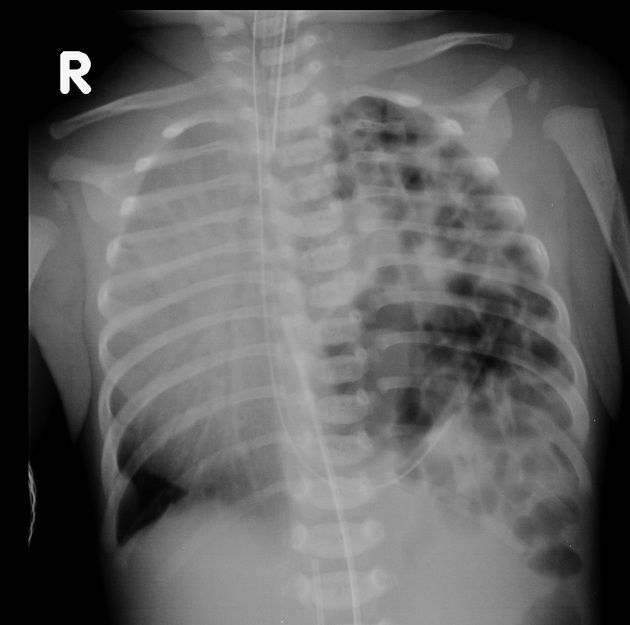

• X quang phổi có bóng hơi dạ dày hay ruột trong lồng ngực, trung thất bị đẩy về bên đối diện, không thấy vòm hoành.

Hình 2. Hình ảnh Xquang ngực của trẻ bị thoát vị hoành bẩm sinh